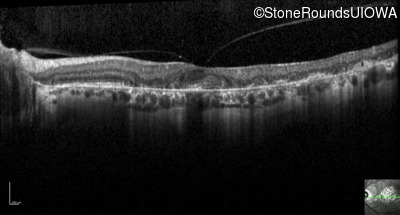

Optical Coherence Tomography - Left - 20/25 -2

Exemplar / OCT Stack

OCT Stack